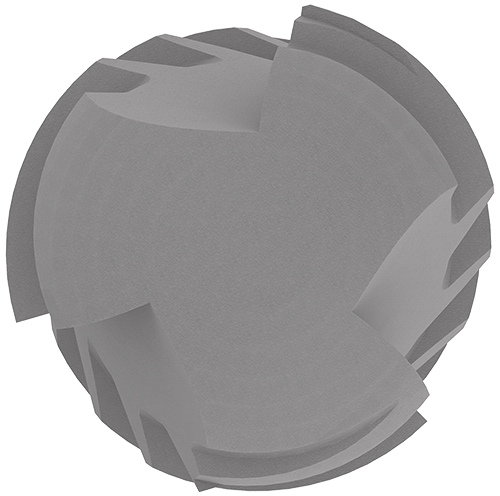

Ápice activo